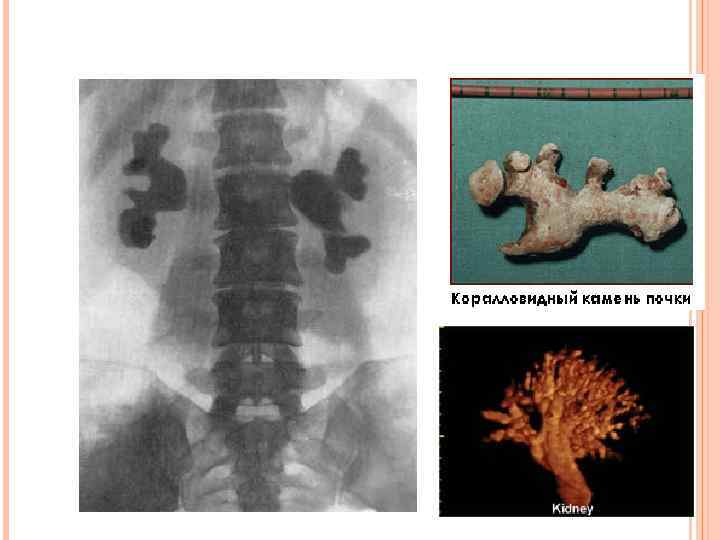

Мочекаменная болезнь

Мочекаменная болезнь